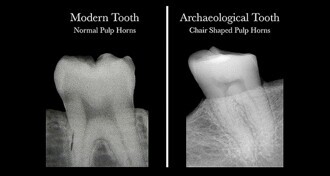

Scientists discover that dental radiographs can reveal vitamin D deficiency

HAMILTON, Ontario, Canada: Human teeth hold vital information about vitamin D deficiency, and Canadian anthropologists have now found that this serious but ...